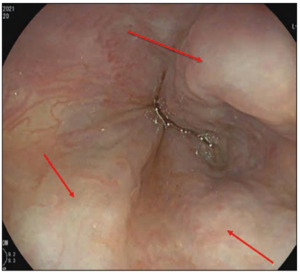

A few days before the fourth cycle of therapy, the patient was hospitalized for an episode of massive hematemesis resulting in a severe hemoglobin decrease with hemodynamic instability, secondary to rupture of esophageal varices. The patient was intubated and placed on mechanical ventilation. Gastric endoscopy was performed, which showed the presence of blood in the gastric cavity from suspected variceal bleeding (Figure 3).

The vasoactive agent, octreotide, was started concurrently with treatment with beriplex (human prothrombin complex), tranexamic acid and red cells transfusion. After prokinetic therapy, a second gastric endoscopy was performed, which showed the presence of esophageal varices F2−F3 (Figure 4).